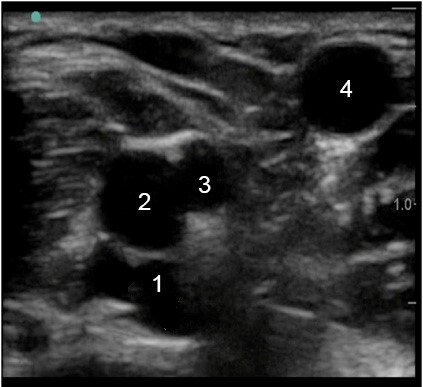

Peripheral IV (PIV) Brachial Vein and Artery and Basilic Vein Image

1. Brachial Vein

2. Brachial Artery

3. Brachial Vein

4. Basilic Vein